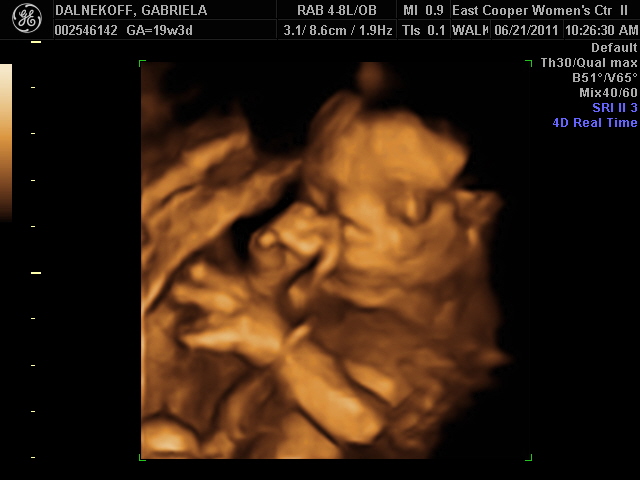

It's a girl! E' uma menininha!

Here is a picture at almost 20 weeks for you guys to see. Steph was right! She was the only one that guessed girl :)

Aqui esta' uma foto da nene com quase 20 semanas para voces verem. A Steph estava certa...ela foi a unica que achava que era menina :)